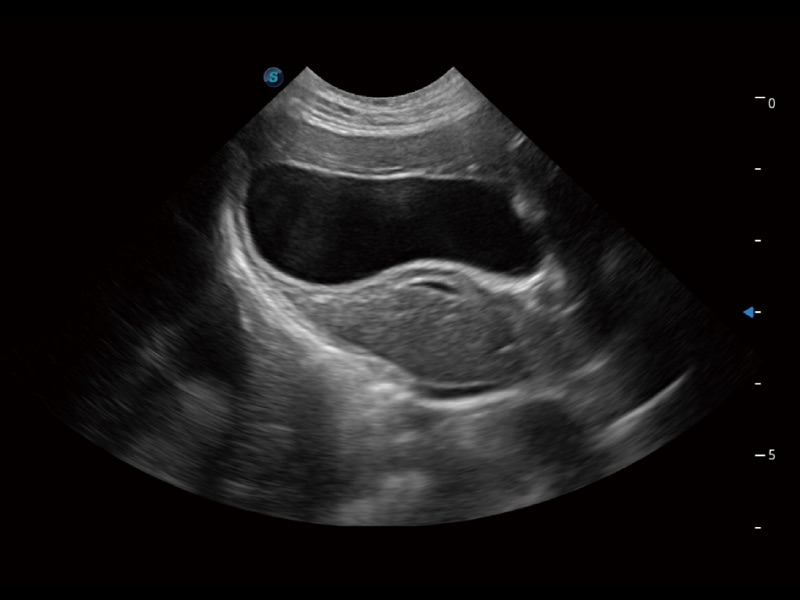

一鍵自動識別膀胱壁及自動測量膀胱容積,不受膀胱形狀和大小的限制,幫助醫(yī)生快速精準(zhǔn)獲得測量的數(shù)據(jù)。